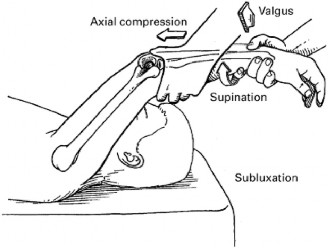

Which of the following is not a usual mechanism by which SLAP tears usually occur?

The correct answer is (D). This is a common mechanism of AC joint pathology including distal clavicular osteolysis.

The most common mechanisms by which a SLAP tear occurs are compression (Answer A) and traction (Answer B). Compression generally occurs when a person falls on an outstretched arm that is slightly flexed and abducted with a tensed biceps. Traction can occur in an anterior, superior, or inferior direction. In the case of this patient, he was falling and caught a tree branch, causing traction in a superior direction. Traction can also occur with overhead throwing (Answer C) or with shoulder dislocation (Answer E). Up to 33% of slap tears, however, have insidious onset.